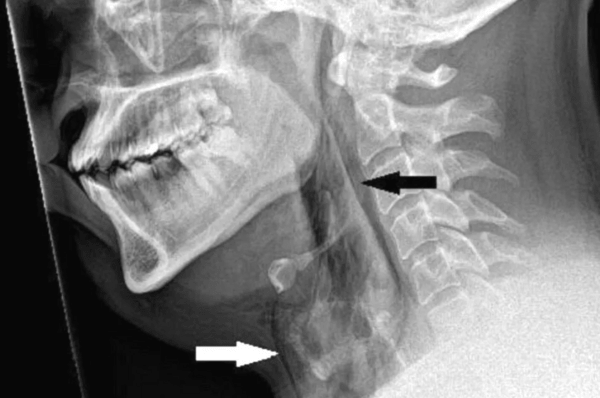

Εξετάζοντας τον περίπου 30 ετών ασθενή, οι γιατροί άκουσαν έναν ήχο όταν άγγιξαν τον λαιμό του. Οι ακτινογραφίες αποκάλυψαν πως «πνίγοντας» το φτέρνισμα προκάλεσε μια ρήξη 2 χιλιοστών στην τραχεία του, σύμφωνα με την έκθεση για το περιστατικό που δημοσιεύθηκε στο BMJ Case Reports.

Οι γιατροί δεν έκριναν απαραίτητο να υποβληθεί σε χειρουργική επέμβαση, αλλά κράτησαν τον ασθενή για παρακολούθηση. Πήρε εξιτήριο αφού του χορηγήθηκαν αναλγητικά και αντιπυρετικά και τον συμβούλευσαν να αποφύγει την έντονη δραστηριότητα για 15 ημέρες. Νέα εξέταση στην οποία υποβλήθηκε έπειτα από πέντε εβδομάδες έδειξε πως είχε επουλωθεί το τραύμα στην τραχεία.